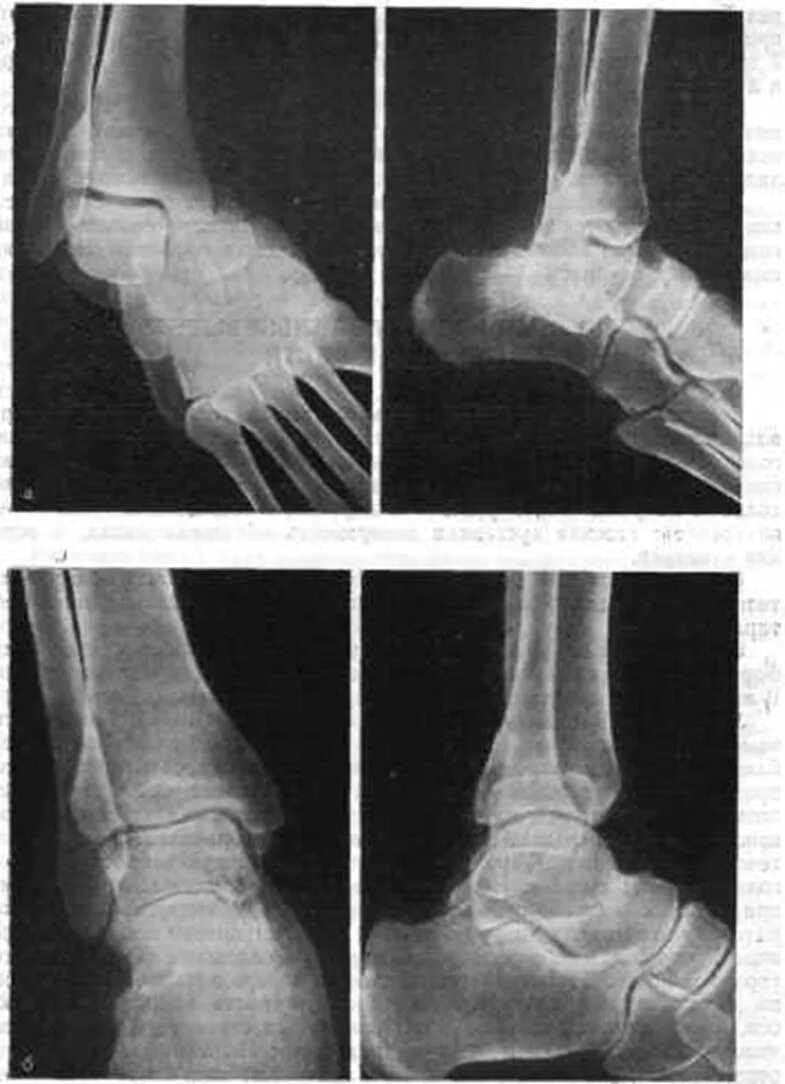

Вывих растяжение ноги